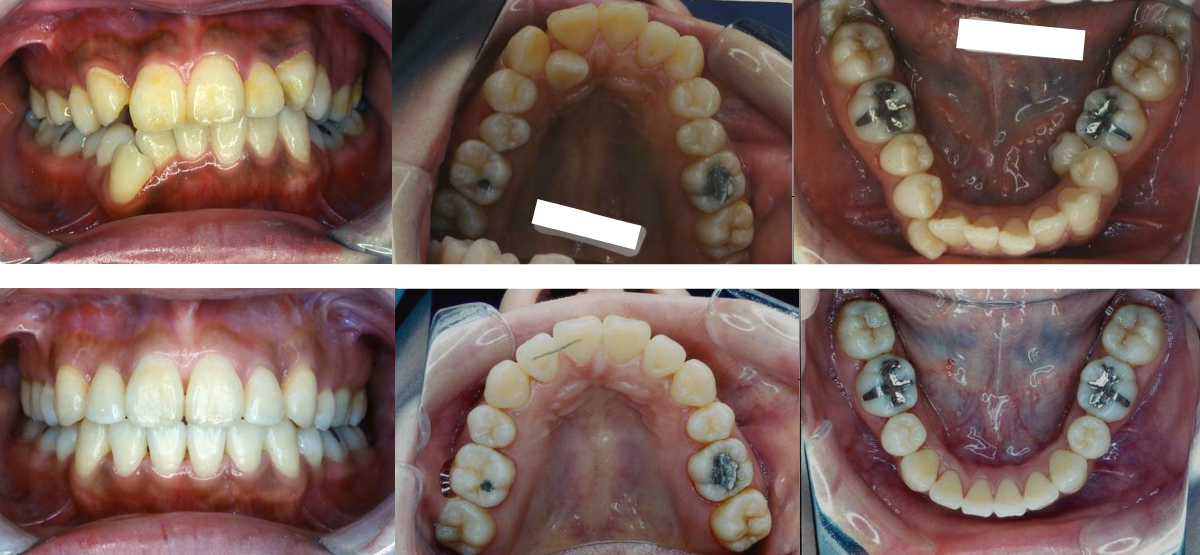

①叢生(でこぼこ)の矯正治療例(30代女性・治療期間2年)

| 年齢・性別 | 30代女性 |

| 治療期間 | 2年 |

| 抜歯 | 上2本、下2本(小臼歯) |

| 治療費 | 50万円(調整費、保定費まで含む総額制) |

| 備考 | インビザライン |

| リスク・副作用 | 痛み・治療後の後戻り・歯根吸収・歯髄壊死・歯肉退縮 |